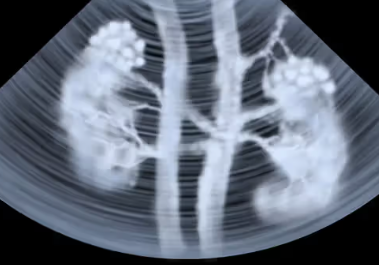

In this series, medical scans—MRI images, X-rays, and other diagnostic views—are transformed into intimate portraits that merge the clinical with the deeply personal. Each work intertwines medical imagery with biographical details, creating a layered visual narrative that honors both the physical realities of illness and the inner lives of those who endure them.

The exhibition features representations of conditions such as multiple sclerosis, lung cancer, hip and knee replacements, a broken wrist, miscarriage, and heartache—each one a story of endurance, adaptation, and faith. The artist wishes to express her gratitude to the patients and their families who entrusted her with creating artworks as unique and special as they are while acknowledging that recovery is never an individual journey; it extends to loved ones who must also heal, grieve, and rediscover vitality in the face of loss or uncertainty.

Mixed media pieces of art derived from the combination of medical scans, surveys from family and friends and genuine creativity from the creator, these artworks are one of a kind.